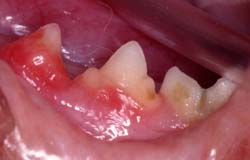

- Synlige symptomer på TR ses som regel ved tandkødskanten, hvor tandkødet er blevet mere rødt og evt. er vokset lidt op over kanten.

Finder man mere end en tand med synlige TR vil der være risiko for, at flere tænder er angrebet.

Billeder af katte med Tooth Resorption (TR/FORL):